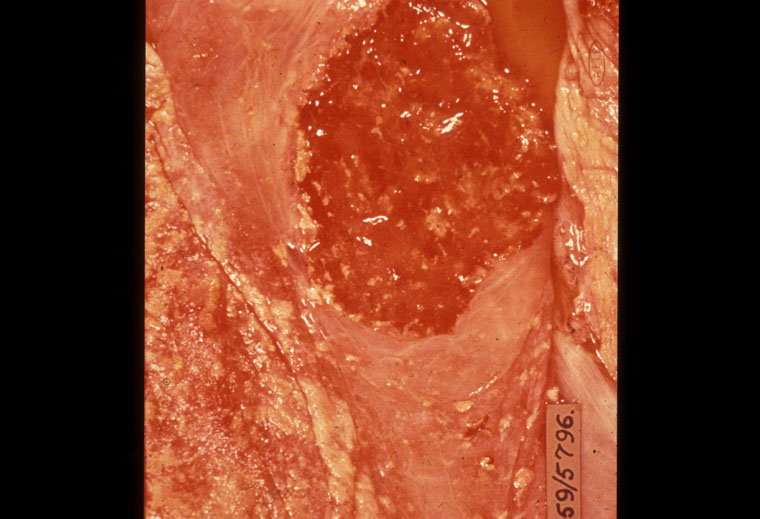

Brucellosis ở bò: Dịch thẩm xuất tại nhau thai và bào thai

Số lượng vi khuẩn nhiễm vào cơ thể động vật cũng là yếu tố quan trọng. Các triệu chứng thường gặp khi nhiễm Brucella abortus là sẩy thai, viêm khớp và sót nhau. Hai nguyên nhân chính dẫn đến sẩy thai là (1)hiện tượng tăng nồng độ alchohol trong nhau thai (chất này có tác dụng kích thích sự phát triển của vi khuẩn Brucella abortus tại nhau thai và bào thai và (2) trong dịch ối không có phản ứng kháng lại vi khuẩn.